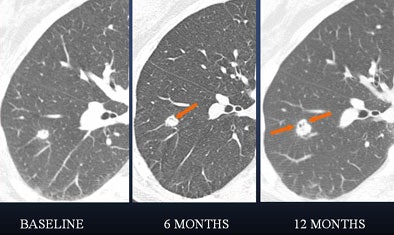

| In a 61-year-old woman a 6-mm nodule was found in the right lower lobe at baseline CT scan. At six-month follow-up, the nodule was determined to be stable in size. At 12 months, however, it had clearly grown in size. The nodule was biopsied and eventually diagnosed as adenocarcinoma. All images courtesy of Dr. Ann Leung. |

"If you look at the 12-month study (61-year-old woman, above), you will appreciate air lucency within that nodule," Leung said. "We're recognizing now as we are scrutinizing nodules much more carefully that the presence of air bronchograms is a concern for malignancy," she said. "If we look back at the first image, at six months, we can see that this lesion also had air bronchogram. We should have been more aggressive in trying to provide a diagnosis for this patient."